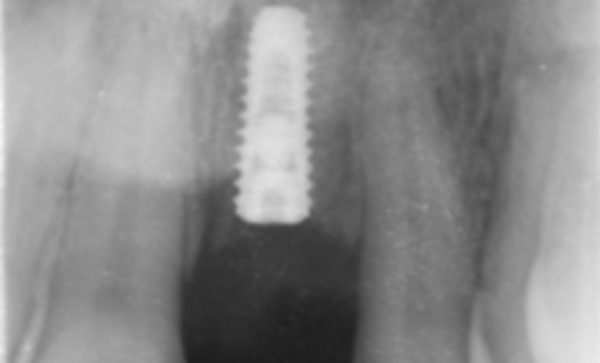

Case 21